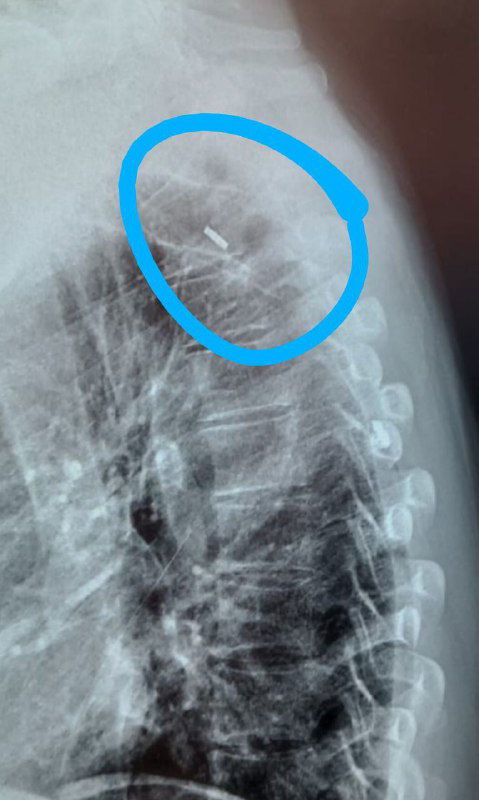

Кейс нейрохирургии: эндоскопическое удаление металлического осколка из грудного отдела позвоночника — рентген, входной разрез, извлечённые фрагменты и эндоскопия.

Краткий обзор причин удаления неугрожающих жизни осколков: хроническая боль, миграция, невозможность МРТ; автор — нейрохирург о пользе удаления.